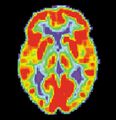

PET scan of a healthy brain - Image courtesy of US National Institute on Aging Alzheimer's Disease Education and Referral Center

Alzheimer's disease (AD) is a progressive, degenerative and fatal brain disease, in which cell to cell connections in the brain are lost. Alzheimer's disease is the most common form of dementia.[2] Globally approximately 1–5% of the population is affected by Alzheimer's disease.[3] Women are disproportionately affected by Alzheimer's disease. The evidence suggests that women with AD display more severe cognitive impairment relative to age-matched males with AD, as well as a more rapid rate of cognitive decline.[4]